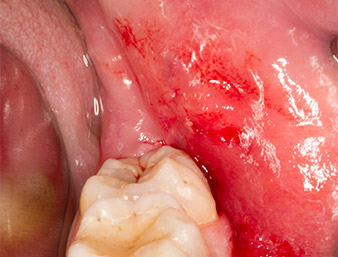

Dopo l'anestesia tronculare e l'anestesia locale, il sito operatorio è stato aperto e il tessuto molle esposto per l'accesso retromolare boccale (Fig. 3).

Il tessuto al di sopra del residuo di radice non era completamente ossificato ed era costituito per la maggior parte da tessuto di granulazione modificato dall'infiammazione (Fig. 4).